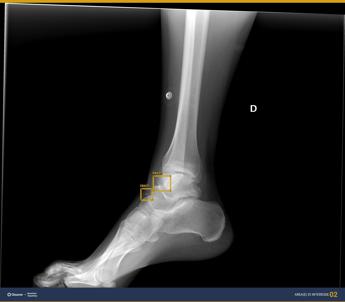

(Adnkronos) – All'ospedale San Camillo di Roma le radiografie le rivede l'intelligenza artificiale. Un assistente virtuale che 'ci butta un occhio' per fornire un second look, una seconda lettura, in tempo reale. La Radiologia di urgenza/emergenza dell'azienda ospedaliera capitolina – informa l'Ao – da circa 6 mesi ha sperimentato l'implementazione di software di Ai nell'ambito della radiodiagnostica, capaci di offrire supporto alla diagnosi per lesioni osteoarticolari e patologie polmonari. La Uosd Radiologia di emergenza/urgenza del San Camillo, diretta da Michele Galluzzo e afferente al Dipartimento Emergenza Accettazione e delle Chirurgie specialistiche guidato da Pierluigi Marini – spiega una nota – gestisce flussi di lavoro estremamente intensi, sia dal punto di vista del numero di pazienti che della complessità degli esami. E' attiva h24 per 365 giorni l'anno ed effettua un numero totale annuo di prestazioni pari a 84.561, di cui 41.792 esami Tc e 35.084 esami radiografici. Questo richiede particolare attenzione nella refertazione, anche nei momenti più sfavorevoli, come ad esempio di notte. A partire da fine 2023, dunque, un team composto da Galluzzo, da Riccardo Ferrari, dirigente medico della Radiologia di emergenza/urgenza e presidente eletto della sezione di Informatica e Ai della Sirm (Società italiana di radiologia medica ed interventistica), e da Annarita Caporaso, direttore dell'Ingegneria clinica, ha avviato gli studi di fattibilità per implementare la dotazione tecnologica della Radiologia d'urgenza con software alimentati dell'intelligenza artificiale, con l'obiettivo di "ottimizzare e migliorare, grazie alle nuove tecnologie, esiti, tempi e utilizzo delle risorse". E' stato quindi acquisito un software che lavora come 'secondo lettore' delle immagini radiografiche, in grado di individuare lesioni osteotraumatiche quali fratture, lussazioni e versamenti, oltre a lesioni focali dell'osso, e di fornire informazioni di supporto al radiologo nel diagnosticare alcune patologie polmonari in condizioni di urgenza, anche in radiogrammi eseguiti in situazioni difficili, per esempio in pazienti allettati. "L'intelligenza artificiale è una tecnologia con un forte impatto nella diagnostica per immagini – afferma Galluzzo – In condizioni di urgenza è un utile supporto diagnostico per il medico radiologo. Importante sottolineare – precisa – che la tecnologia non sostituisce il medico, ma rappresenta un valido strumento nell'ottica del miglioramento delle performance diagnostiche e gestionali". "In un ambito fortemente tecnologizzato come la radiodiagnostica – aggiunge Ferrari – l'implementazione di tecnologie basate su intelligenza artificiale permette al medico radiologo di utilizzare automazioni e supporto alla diagnosi per poter correttamente interpretare le immagini e diagnosticare le patologie. L'utilizzo di tecnologie di supporto alla diagnosi nella radiologia d'urgenza, e in un reparto ad alta intensità di afflusso come il nostro, vuol dire fornire a colleghi e pazienti le tecnologie più all'avanguardia per la diagnosi e la cura". E' stato necessario un training specifico del personale medico e tecnico – si evidenzia nella nota – con precise istruzioni sui vantaggi e sui limiti dell'uso di queste tecnologie. "Riteniamo che il sistema acquisito abbia un ottimo rapporto qualità prezzo – rimarca Caporaso – aspetto anche quest'ultimo rilevante in un'ottica di garanzia della qualità delle prestazioni erogate nel rispetto comunque del contenimento della spesa sanitaria. Siamo pronti ad acquisire altri software basati sull'Ai che permettano di supportare il radiologo anche in patologie tempo dipendenti, con una prelettura e segnalazione prioritaria dei reperti di particolare interesse e urgenza". Un progetto che si incardina in quello più ampio fortemente voluto dalla direzione strategica – si legge – di portare l'azienda ospedaliera San Camillo-Forlanini a essere prima tra le Ao laziali nell'utilizzo di tecnologie basate su intelligenza artificiale. —salutewebinfo@adnkronos.com (Web Info)